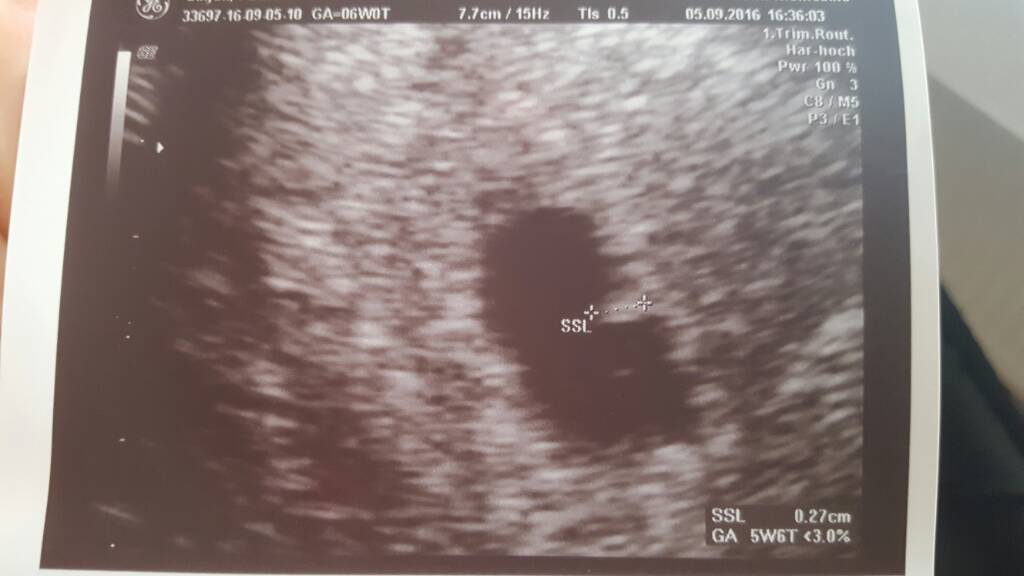

Wklejam zdj. Mojej fasolki z dzisiaj. Z ost miesiaczki 6+0, z usg 5+6, wiec w sumie sie zgadza bo mam regularne cykle co 29 dni. serduszko juz bilo

Moja dzidzia

Sam początek 6tyg, a serduszko juz biło, zarodek 3mm